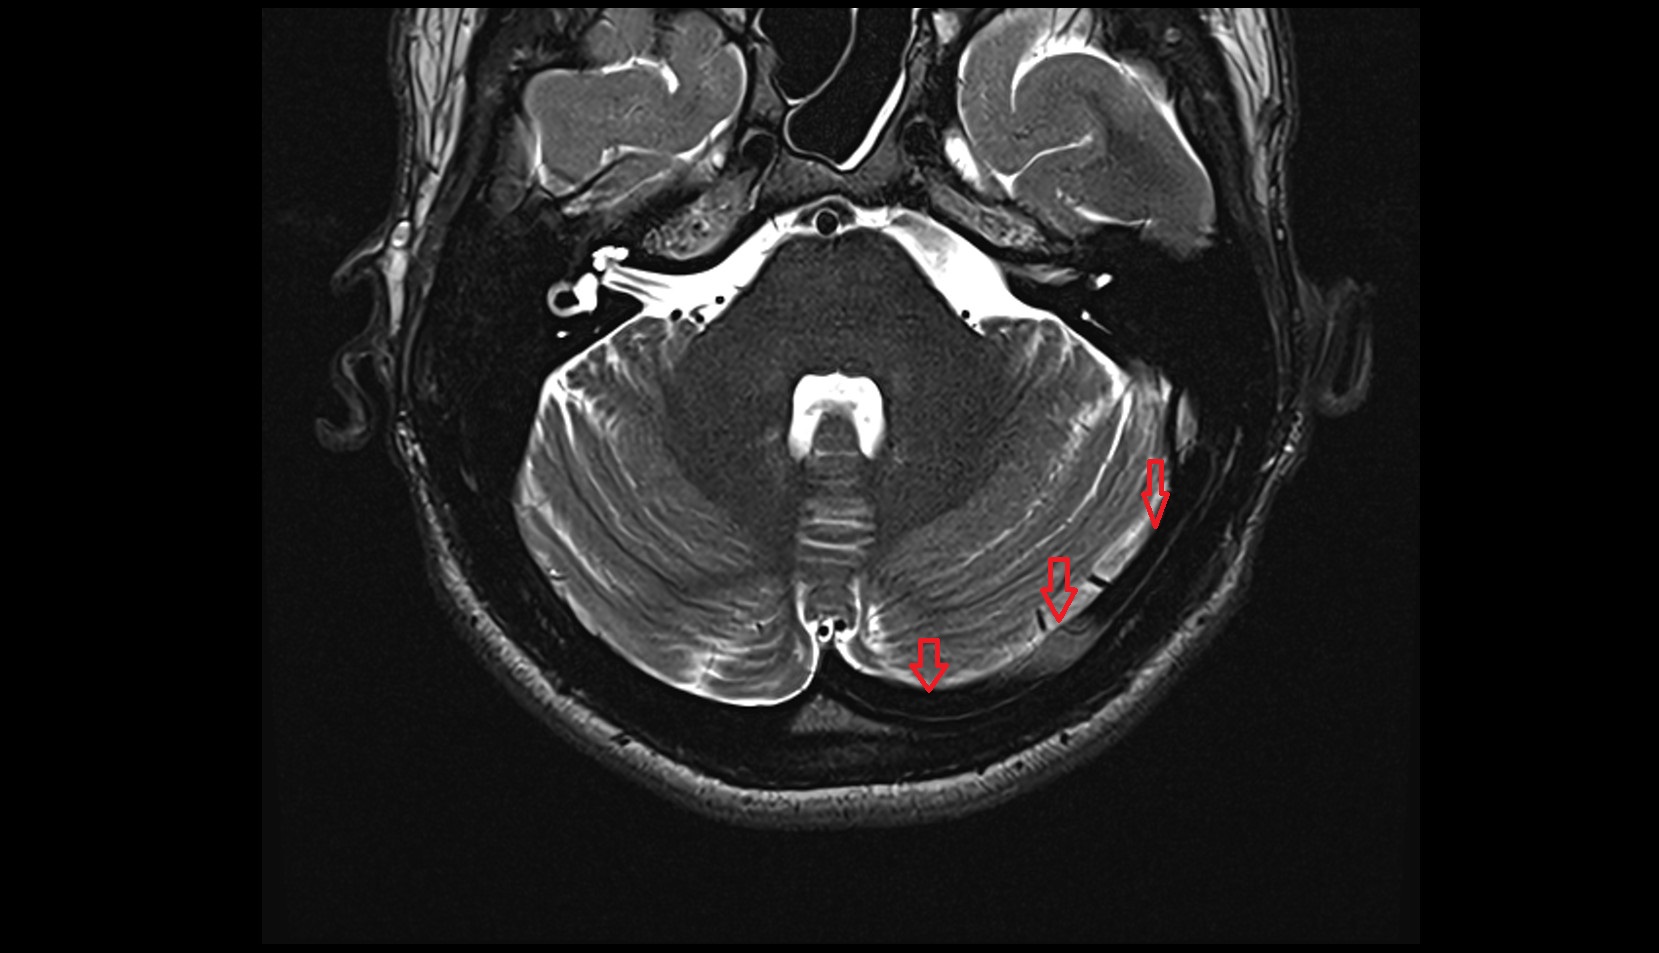

- Cerebellar tonsil (H IX)

- Tonsil of cerebellum